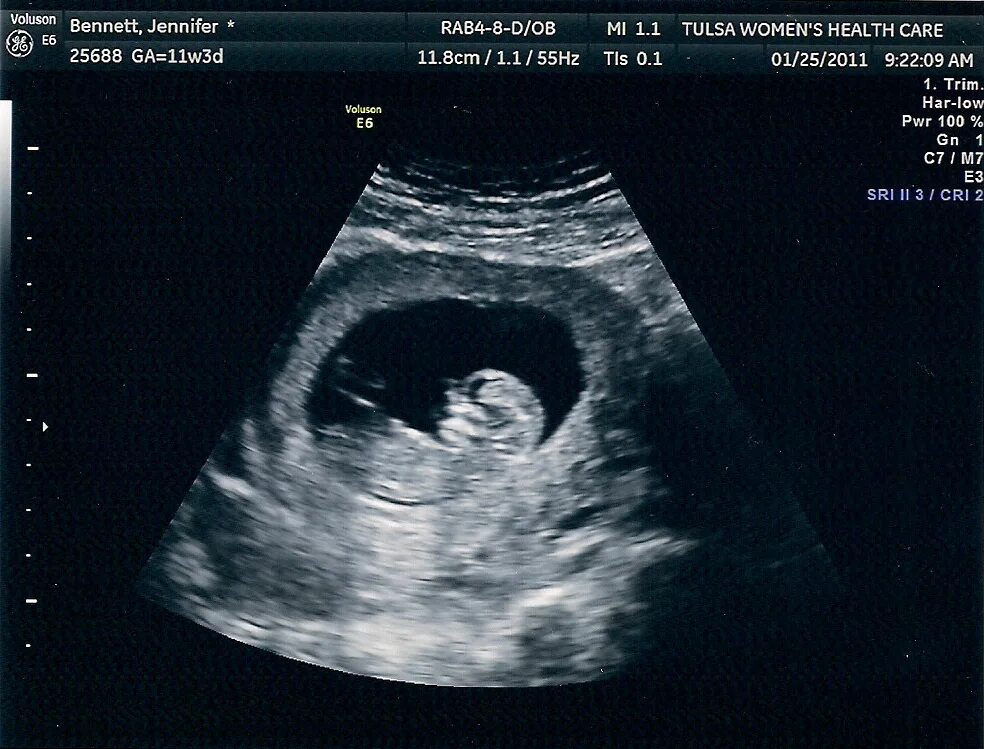

7 12 недель